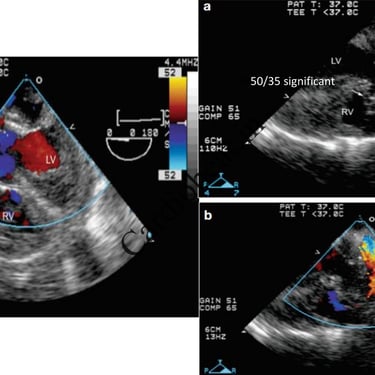

Truncus Arteriosus